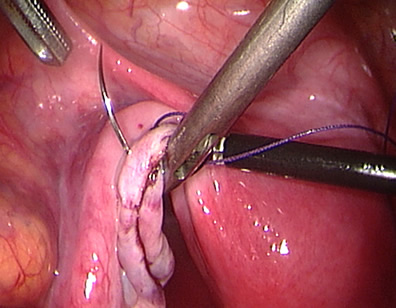

This lady had an ectopic pregnancy in the left tube. See the dilated area in the tube.

The tube is being opened to reveal the pregnancy